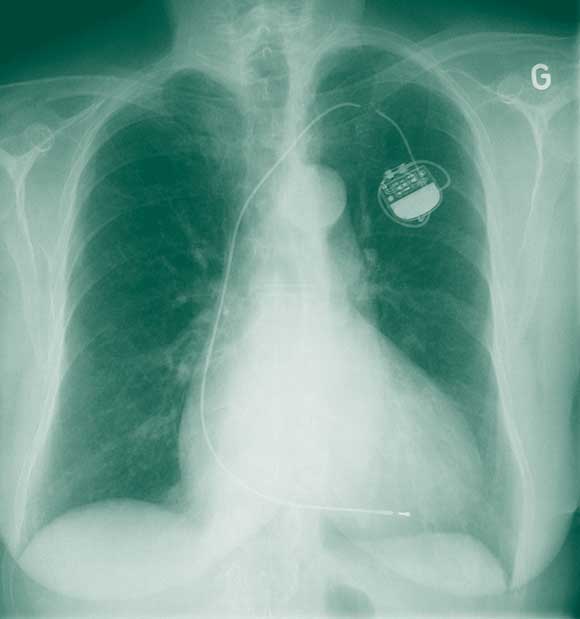

Seven years later, she presented with fatigue and presyncope of 1 week’s duration. She had also noticed contractions of the pectoral muscles on the left side of the chest. An electrocardiogram (Box 1) showed evidence of ventricular undersensing and non-capture, and a chest x-ray (Box 2) revealed complete fracture of the pacemaker lead. The pacemaker was replaced, and a new lead implanted using the cephalic vein cutdown approach.

The patient’s medical record indicated that, 8 months previously, when she developed a cough, a chest x-ray had been performed by her physician. At around the same time, a routine check of the function of her pacemaker indicated that it was functioning normally. Re-examination of the x-ray revealed signs of lead erosion (Box 3) which had gone unnoticed. Thus, despite significant damage to the lead, pacemaker function may be unaffected.